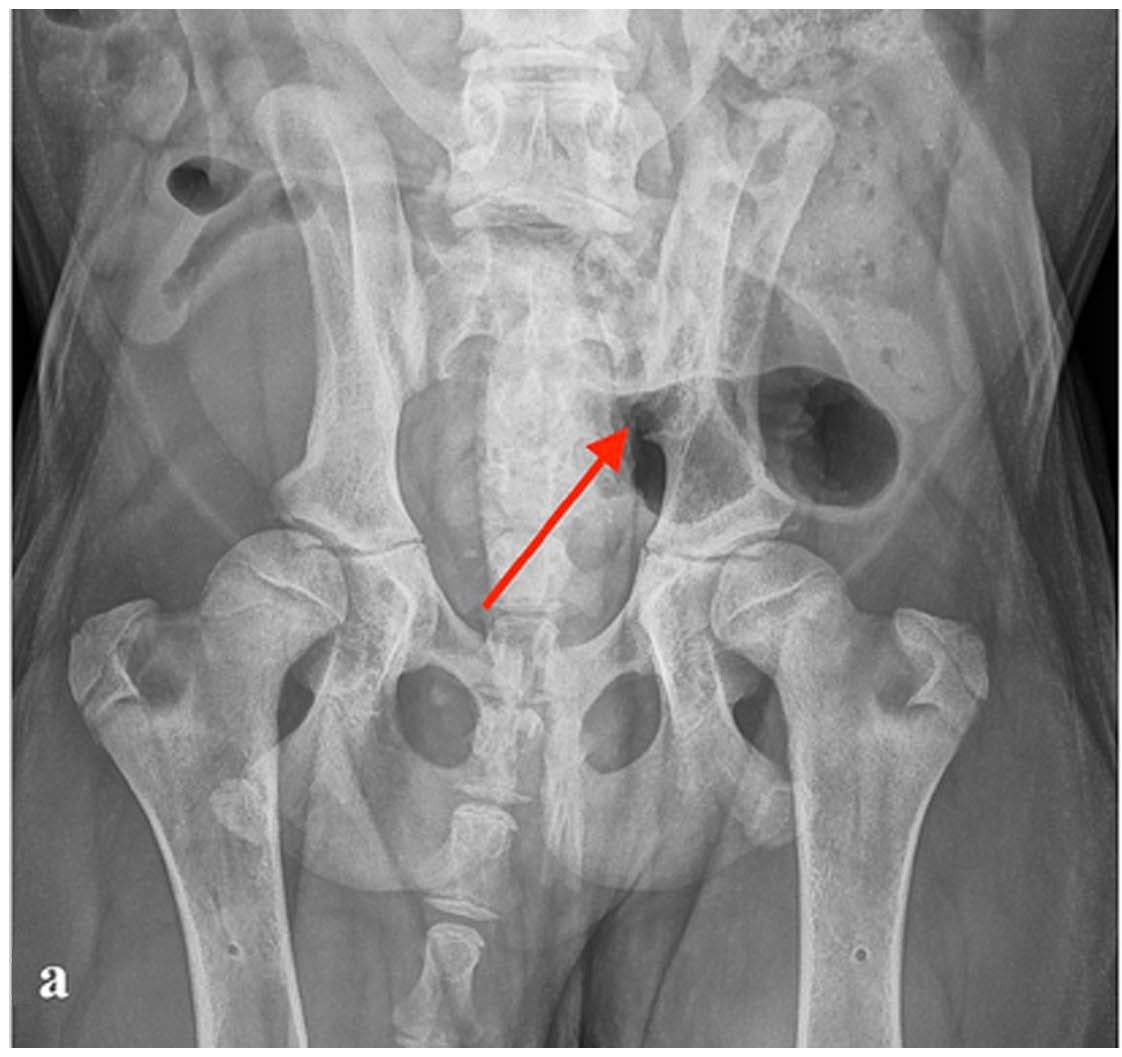

镇静后拍摄了腰椎和骨盆X光片。X光片显示左侧骶髂关节有侵蚀性病变,以及轻度髋关节松弛(下图)。

↑ (a)腹背位X光片显示左侧骶髂关节有侵蚀性病变(红色箭头)。

CT显示双侧骶髂关节表面有多处小的、随机分布的囊状和不规则形状的凹陷缺损,周围有明显的硬化(下图)。还观察到骶髂关节间隙不对称增宽。左侧病变严重,右侧病变中等。X光和CT还显示髋关节有轻度犬髋关节发育不良的改变。